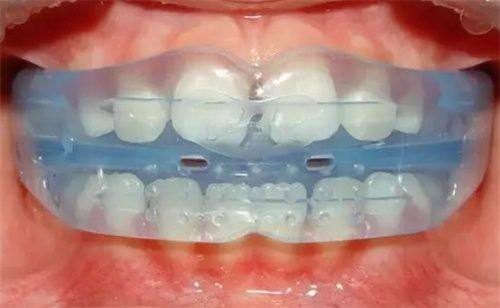

不过,成人整牙和青少年整牙还是有一些区别的。成人的牙齿和颌骨已经基本发育完成,矫正的难度和风险相对较大,治疗周期也会更长。而且,为了保持矫正成效,成人需要佩戴更长时间的保持器。

成人整牙面临着一些挑战。首先,牙齿移动速度相对较慢,这就意味着矫正周期会延长。其次,成人可能存在一些口腔问题,如牙周炎、龋齿等,需要在矫正前进行治疗,以确保矫正的顺利进行。

但成人整牙也有自己的优势。成人具有更强的自律性,能够更好地配合医生的治疗,按时佩戴矫治器和保持器。而且,成人对美的追求更加明确,矫正的动力也更足。